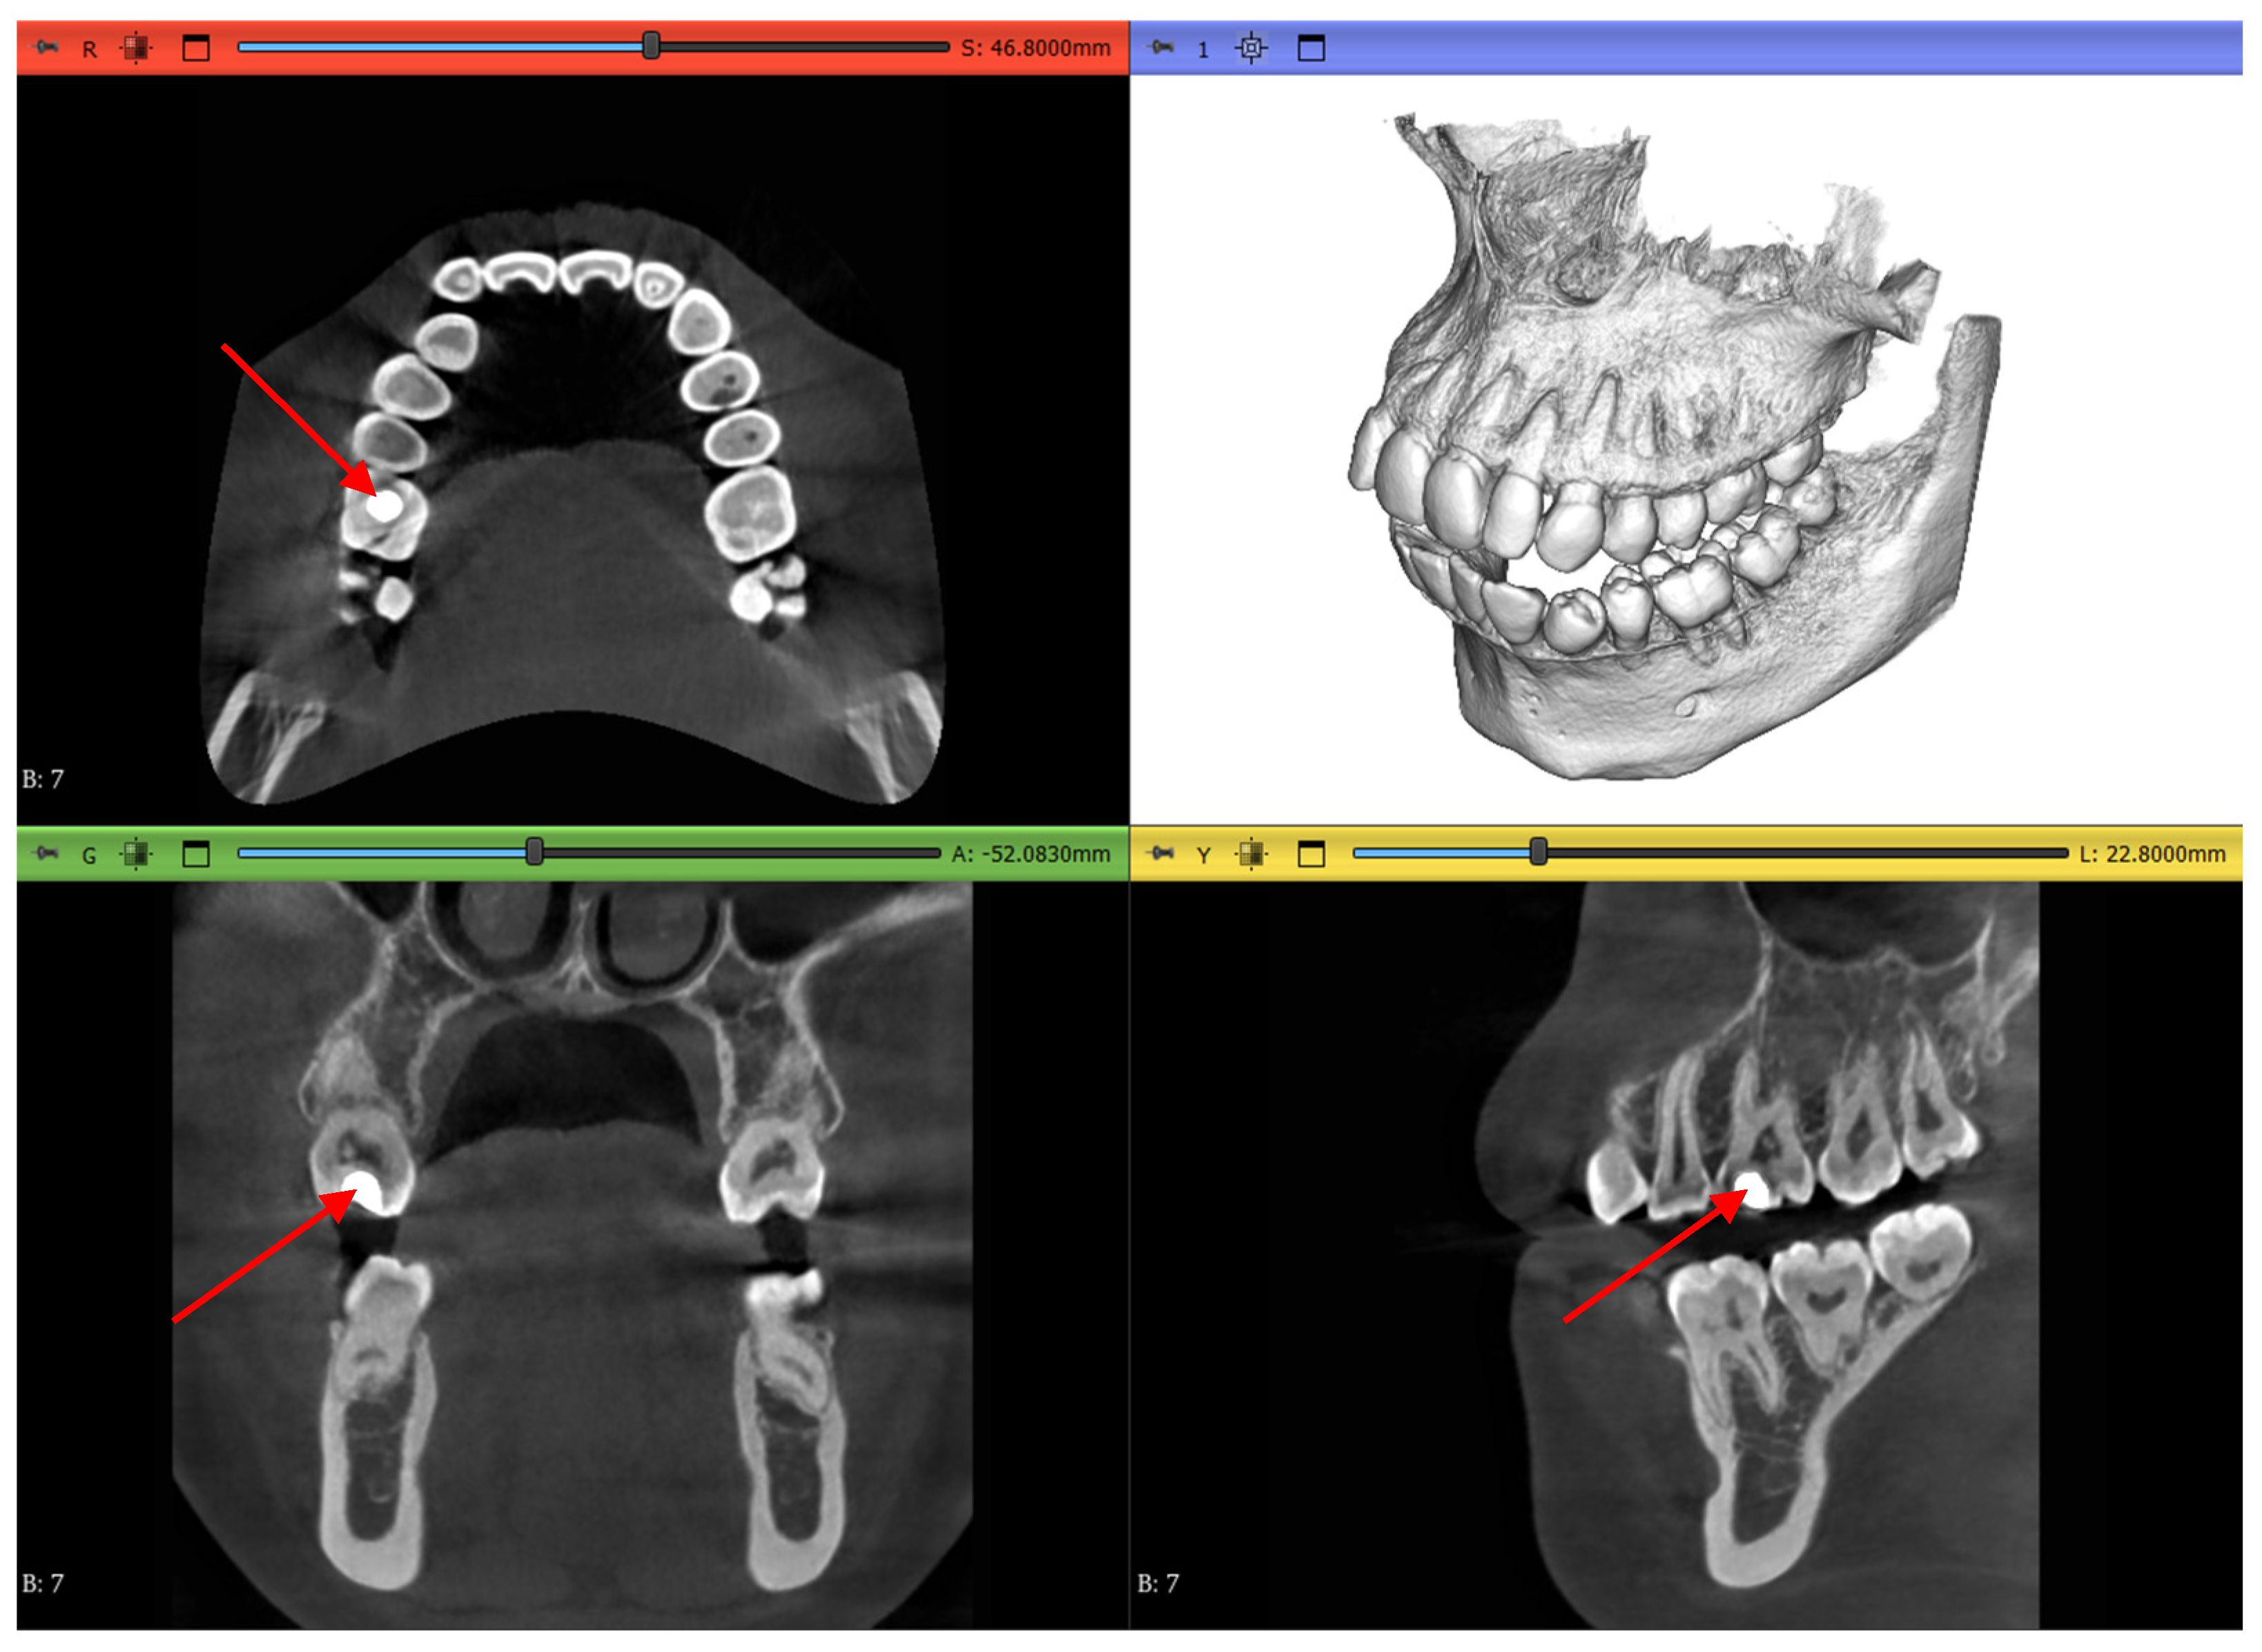

Dataset 1 is the most straightforward of all, with a teeth spacer to avoid overlapping in the scans and no abnormalities except an amalgam restoration, as shown in Figure 4 by a red arrow, in a maxillary first molar which is not of interest to this study.

Figure 4.

Dataset 1 of the study with red arrows showing the amalgam restoration.

Dataset 2 is slightly more challenging, as it does not contain mandibular teeth. Figure 5 shows that the maxillary teeth are newly erupted with open apexes, as shown by a green arrow, have restorative operations shown by blue arrows, an impacted second premolar, as shown by red arrows, and an unerupted third molar, as shown by black arrows.

Figure 5.

Dataset 2 of the study showing open apexes by a green arrow, restorations by blue arrows, impacted molar by red arrows, and unerupted molar by black arrows.

Dataset 3 presents the most challenging obstacle to the workflows, as it includes braces, and the maxillary second molar chosen has 4 roots instead of the more common 3-root configuration, as shown in Figure 6 by the red arrow.

Figure 6.

Dataset 3 of the study with a red arrow pointing to the 4-rooted maxillary second molar.